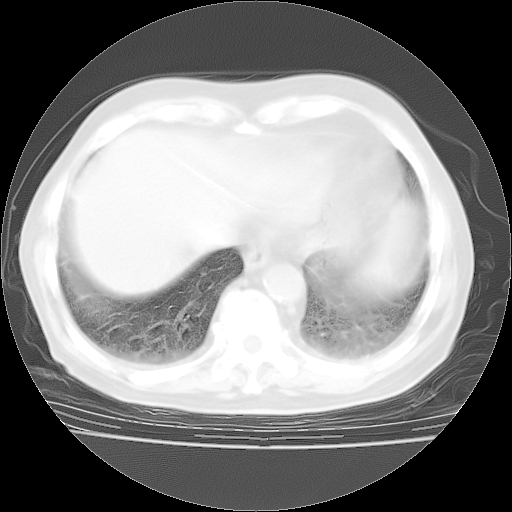

4月28日肺部CT——再次出现类似去年5月9日——透光度降低,“间质性”改变。

4月28日肺部CT——再次出现类似去年5月9日——磨玻璃样、间有“粟粒样”改变。

4月28日肺部CT